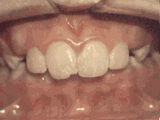

深覆合,咬牙时,上牙盖住下牙的部位过多,影响美观,经过矫正的牙齿是这样的~

深覆盖,咬牙时,上牙差不多完全把下牙挡住了,黄飞鸿的弟子牙擦苏就是这类,经过矫正后的牙齿是这样的~